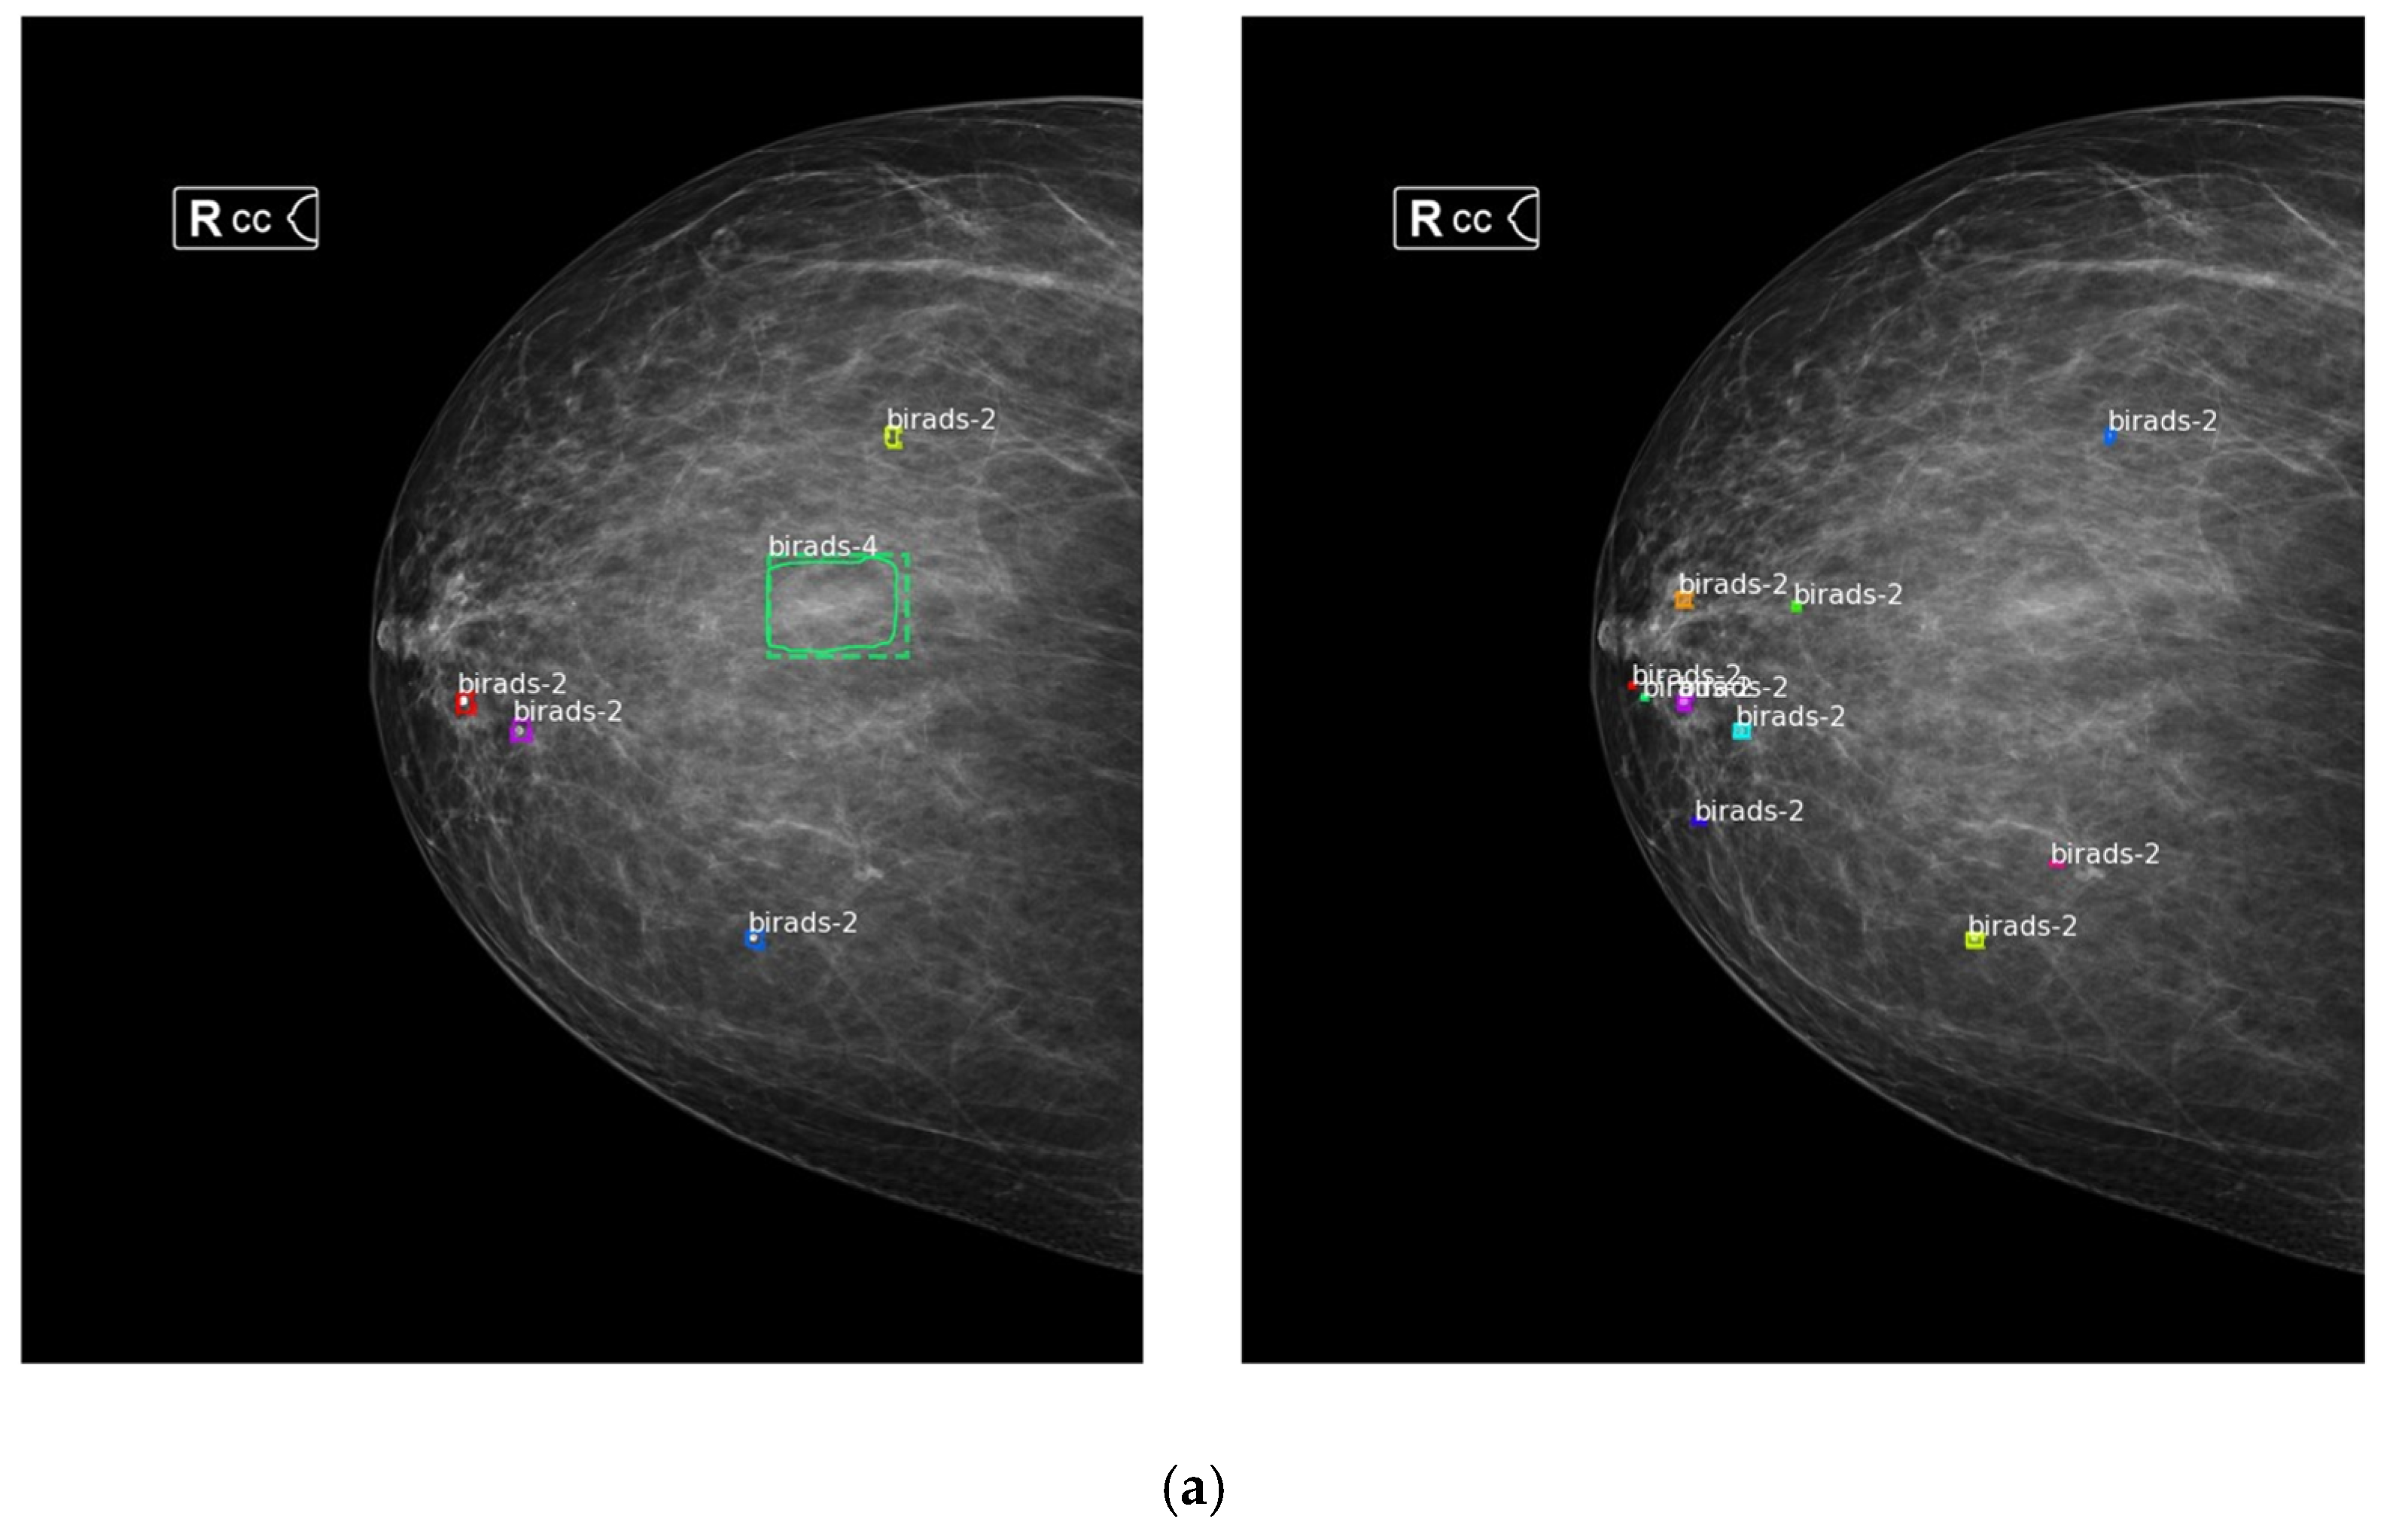

In the second part of the experiment, we compare the performance of detections using the BI-RADS lexicon. The object detection model is trained on 4124 patches generated from training data of 1567 mammography images. The remaining patches that do not contain any labeled masses/micros are discarded. In addition, for comparison, we trained the original Faster R-CNN model on 1567 whole mammogram images. To ensure fairness, we trained both models for 300 epochs on the same training conditions (e.g., the same GPU and machine). Figure 6 shows the results of our two-stage model and the original Faster R-CNN model on sample images. It is seen that our two-stage model can detect BI-RADS 2 far better than the ‘one-stage’ model because more information can be preserved by generating patches from extracted RoI. This validates that our method effectively solves the issue of the huge ratio difference of small lesions to the original input size by avoiding the proportion of breast lesions from being underrepresented. Moreover, our model eliminates false detections, which contributes to significant performance improvement, as seen in Figure 6a where original Faster R-CNN falsely detected BI-RADS 4.

Figure 6. Performance difference between one stage (on the left) and two-stage (on the right) Faster R-CNN detection models: (a) inference results on sample data #1; (b) inference results on sample data #2.